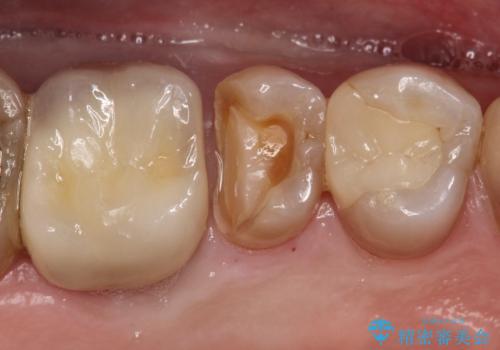

【MTAを用いた生活歯髄療法】神経に到達する深い虫歯

- 以前入れていた、詰め物が取れたことを主訴に来院されました。

虫歯が深く、神経の部屋まで達していました。

術前の検査から、神経が保存できる可能性が高いため部分的断髄法を選択し治療を行いセラミックインレーにて修復しました。

褐色の歯質を認めますが、テトラサイクリンによる変色のためカリエスの残存はありません。